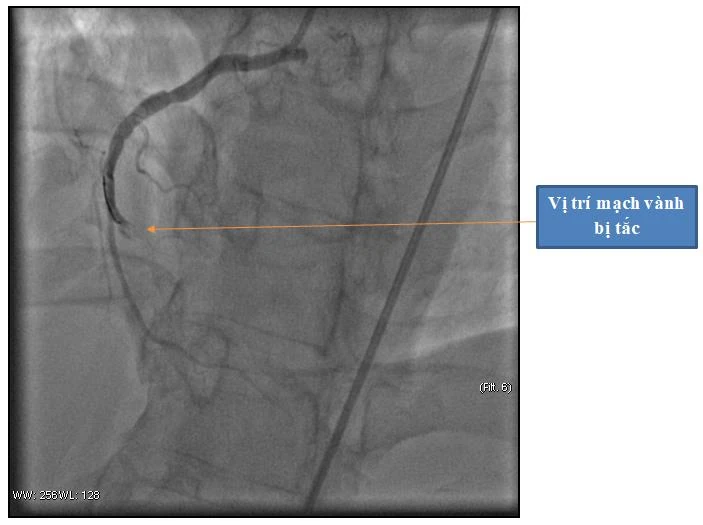

Hình ảnh động mạch vành phải bị tắc hoàn toàn

Người bệnh nhanh chóng được chuyển vào phòng can thiệp tim mạch để chụp và can thiệp mạch vành tái thông mạch vành bị tắc. Kết quả cho thấy động mạch vành phải bị tắc hoàn toàn. Ekip can thiệp đã tiến hành đặt máy tạo nhịp tim cho người bệnh và đặt 1 stent vào vị trí bị tắc nhằm tái thông động mạch vành.